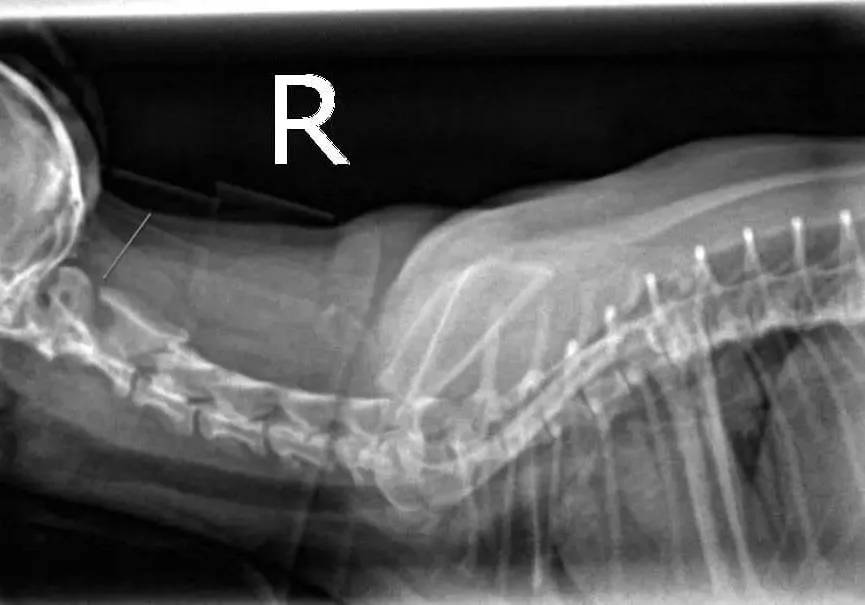

Below are radiographs of Gracie before and after her neck splint was placed. Note the large space between the first two bones in Gracie’s neck prior to reduction.

After Placing the Splint

Gracie after placing a splint. Note that the subluxation is reduced.